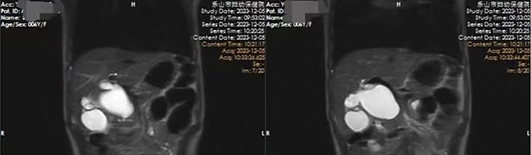

芯芯(化名)于2023年12月5日凌晨因“腹痛伴嘔吐3天”急診收入我院小兒外科。醫(yī)生仔細(xì)詢(xún)問(wèn)病史、查體并結(jié)合輔助檢查結(jié)果,診斷為先天性膽總管囊腫。經(jīng)與家屬充分溝通,完善各項(xiàng)術(shù)前準(zhǔn)備后,由院長(zhǎng)包平倩帶領(lǐng)小兒外科團(tuán)隊(duì)成功為患兒實(shí)施腹腔鏡下先天性膽總管囊腫切除膽道成形術(shù)。

據(jù)了解,患兒術(shù)中膽總管呈現(xiàn)囊性擴(kuò)張,最大直徑約5cm,且囊性擴(kuò)張部分與腸管及周?chē)M織粘連緊密,極大地增加了手術(shù)難度。小兒外科手術(shù)團(tuán)隊(duì)?wèi){借著精湛的技藝完成剝離,切除囊腫,順利完成手術(shù)。術(shù)后在醫(yī)護(hù)團(tuán)隊(duì)的精心照護(hù)下,患兒恢復(fù)良好,目前已康復(fù)出院。